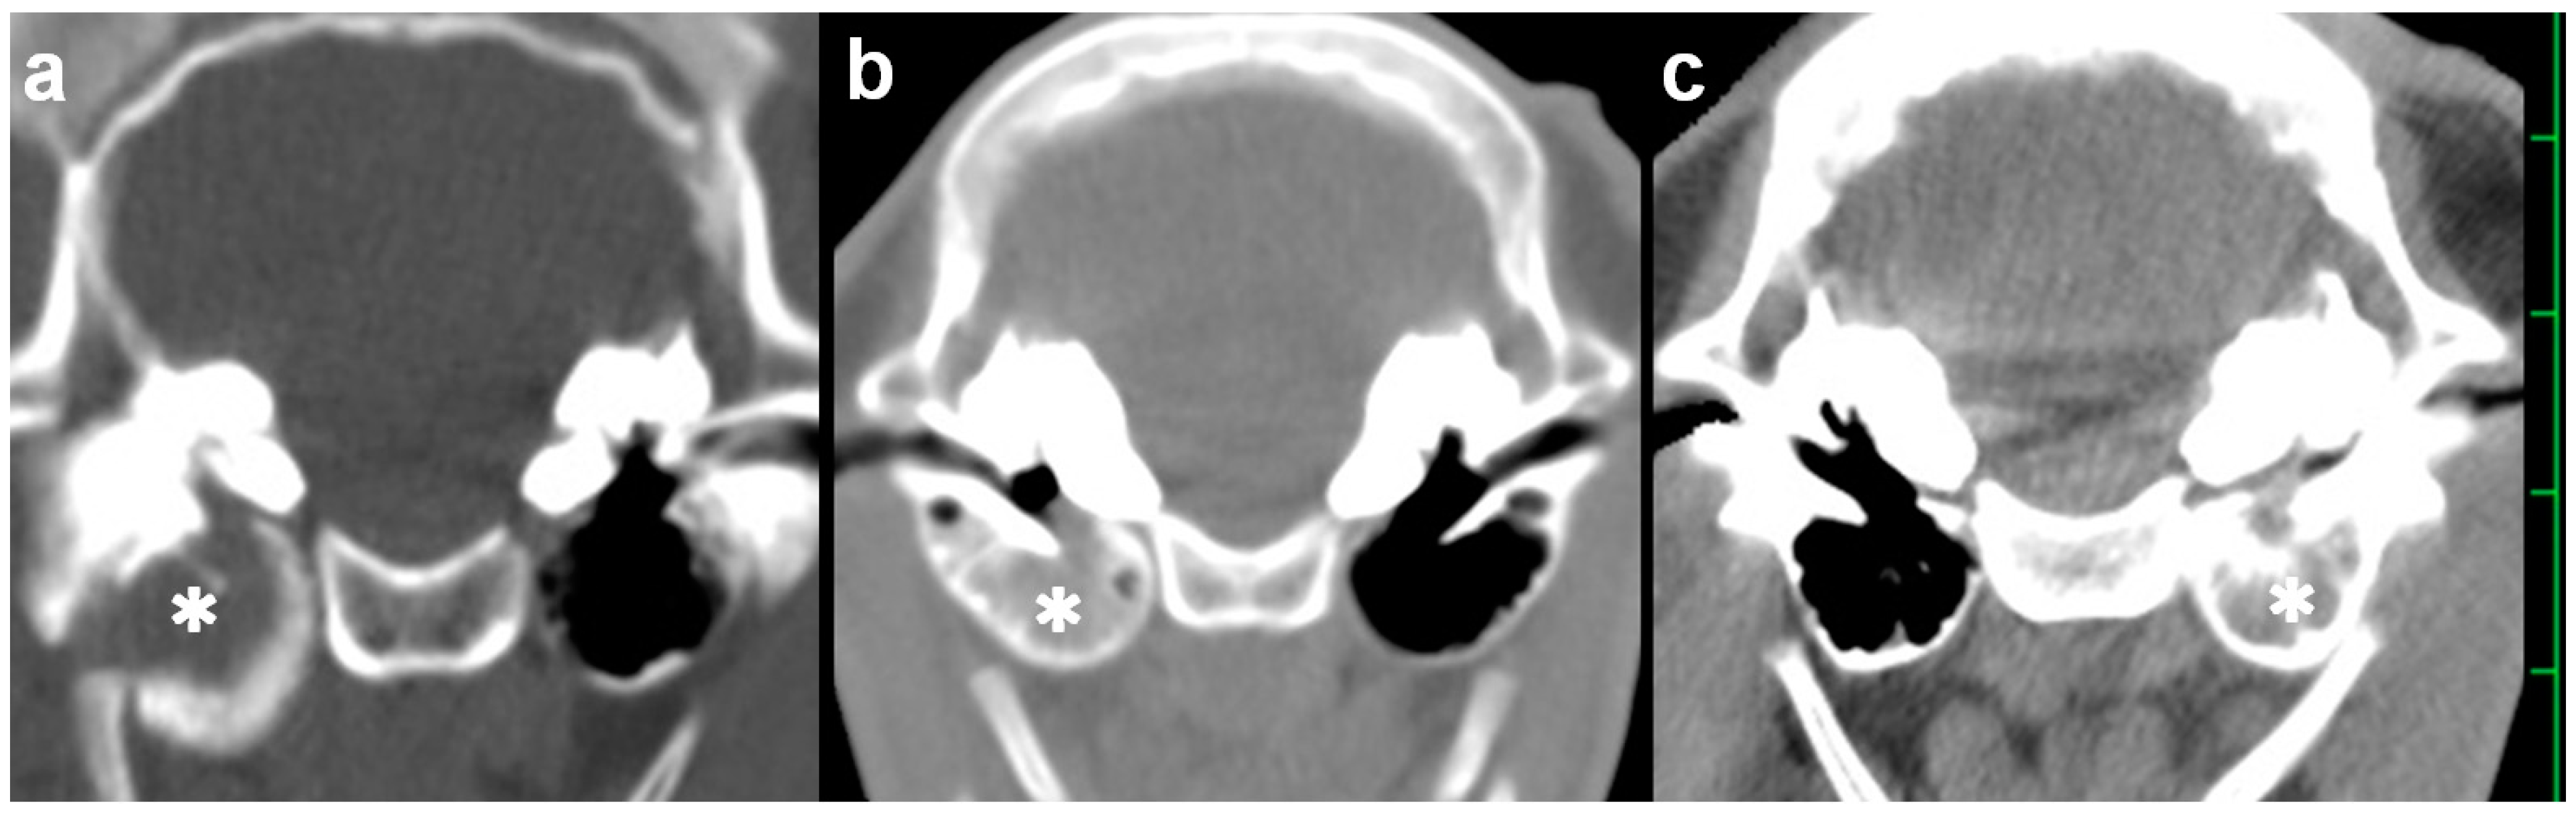

On admission, CT confirmed an accumulation of hyperattenuating contents into the entire cavity of the right tympanic bulla. On the transverse section, the wall structures were entirely hypoattenuating, and thick and rounded in shape due to being extended medially and ventrally (Figure 1a). On the sagittal section demonstrating the right tympanic bulla, the hyperattenuating contents were included in the oblong tympanic cavity due to being extended cranially and ventrally (Figure 2a). No abnormality was evident in the left tympanic bulla. The height, width, and length of the right tympanic bulla were 33.0, 27.2, and 29.2 mm, respectively, and tended to be large compared with those in the opposite left tympanic bulla (24.8, 25.7, and 24.2 mm, respectively) and the measurements (mean ± standard deviation) from five Holstein calves (25.9 ± 4.0, 25.9 ± 2.2, and 24.0 ± 3.3 mm, respectively) (Table 1). Compared with the maximum thickness of the ventral walls in the ears of five Holstein calves (1.9 ± 0.4 mm), the values increased severely in the right affected tympanic bulla (10.9 mm), and slightly in the left tympanic bulla (3.4 mm). Based on quantitative evaluation, the extension in the ventral wall contributed to the larger height of the right tympanic bulla.

A 1-month-old male Japanese Black calf with a body weight of 35 kg suddenly presented a head tilt toward the right, right ear droop, and bilateral horizontal nystagmus. Severe depression was also evident, together with declined physical performance. The calf’s difficulty in standing was suspected to be associated with vestibular ataxia. On admission, because of the quick development of the clinical signs, the severity of the neurological findings was scored 7 [9]. On the preoperative CT, the hyperattenuating contents were seen in the entire right tympanic bulla, in which the wall structures were not thickened and extended (Figure 1b). No difference between the left and right tympanic bulla was found in the height (17.4 mm vs. 15.7 mm), the width (28.5 mm vs. 27.2 mm), the length (26.1 mm vs. 23.0 mm), or the thickness (1.6 mm vs. 2.4 mm), respectively (Table 1). These four values were almost similar to the measurements from the five Japanese Black calves (in order, 21.0 ± 2.0, 26.2 ± 2.6, 22.6 ± 2.4, and 1.9 ± 0.3 mm, respectively).

A 2-month-old male Japanese Black calf with a body weight of 45 kg had developed a head tilt toward the left and left ear droop roughly 10 days previously. Neither depression nor abnormal physical performance were evident. A therapeutic response could not be obtained from a single injection of tilmicosin phosphate solution (10 mg/kg, SC; Micotil300, Elanco Japan, Tokyo, Japan) followed by the administration of an oxytetracycline hydrochloride solution (5 mg/kg, IM, q24, 7 days). On admission, the severity of the neurological findings was scored 2 [9]. The preoperative CT revealed that the left tympanic bulla was slightly extended ventrally and included the entirety of the hyperattenuating contents into the cavity, despite the right tympanic bulla not being abnormal (Figure 1c). No difference between the left and right tympanic bulla was found in the width (25.8 mm vs. 27.7 mm, respectively) or the length (23.7 mm vs. 22.4 mm, respectively), although the height of the right tympanic bulla (21.2 mm) was slightly extended compared with that of the left tympanic bulla (18.4 mm) (Table 1). The thickness in the ventral wall of the left tympanic bulla (5.1 mm) was larger than the measurements from the five Japanese Black calves.

Figure 1. Transverse computed tomography of the skull examined preoperatively ((a) Case 1; (b) Case 2; and (c) Case 3). The hyperattenuating materials (asterisk) are seen within the tympanic cavity. The scale is 25 mm.